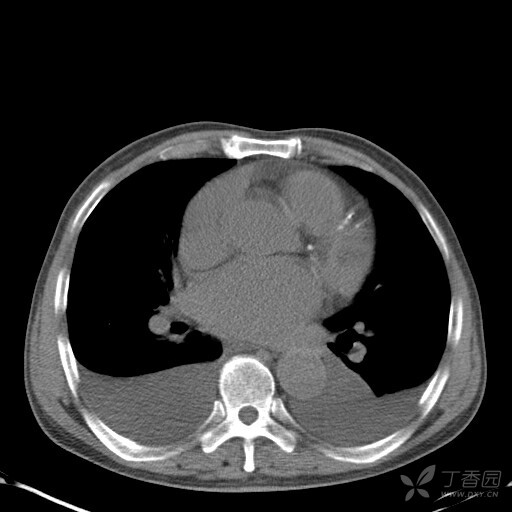

胸腔积液的ct

术前胸部ct示胸腔积液

右侧胸腔积液

ct示右侧大量胸腔积液,当天行微创胸腔闭式引流术.